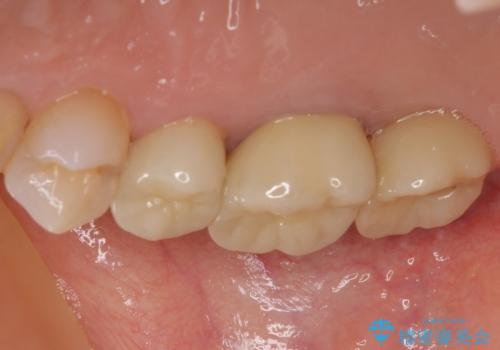

治療中の仮歯も頻繁に壊れておりましたが、インプラントの土台が歯肉上に出てからは咬み合わせが安定し、仮歯が壊れることもなくなりました。